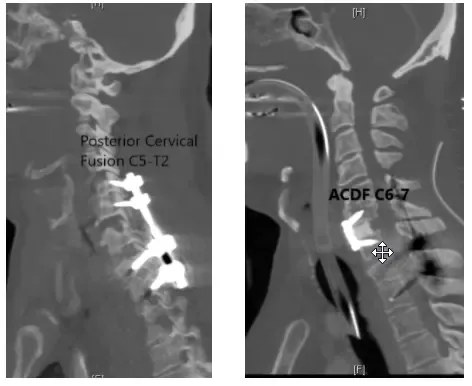

Fue llevado inmediatamente al quirófano, donde la dislocación fue reducida. Debido a la dislocación, la cápsula y el disco del mismo nivel resultaron dañados y la columna vertebral quedó inestable.

Para recuperar la estabilidad, la columna vertebral se fusionaba tanto por delante como por detrás usando placa, tornillo y varillas. Se realizó discectomía cervical anterior y fusión (ACDF) C6-7 con fusión espinal posterior C5-T2.